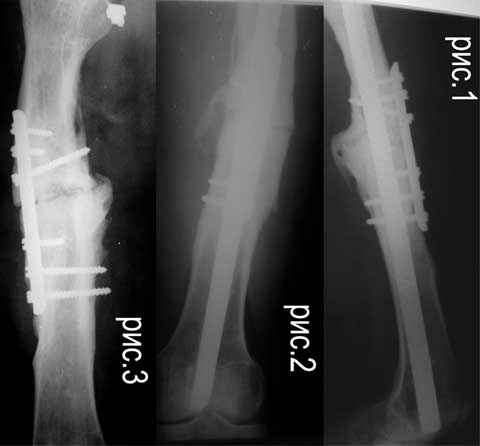

Re: ложный сустав средней трети бедра

Alexander Chelnokov 16 Декабрь 2006, 09:17

Если нет инфеекции и укорочения, то закрытое штифтование с блокированием должно решить проблему. Хотя, видимо, стержень можно ввести как есть, пластину лучше убрать. Инфекция или укорочение при той же окончательной фиксация потребуют дополнительных мер.

Отправитель: Дрягин 16 Декабрь 2006, 12:39

Полностью согласен с Александром.Единственно Вы не акцентировали с рассверливанием или без.Я бы с рассверливанием.

Отправитель: Alexander Chelnokov 16 Декабрь 2006, 14:29

Судя по картинке - достаточно лишь стабилизировать. IMHO здесь рассверливание большого самостоятельного зачения не имеет. Канал должен быть чуть шире выбранного стержня. Если для этого придется рассверлить - то и ладно, если и так широкий - тоже не беда. Стержень взять диаметром 12-13 мм. Если укорочения нет - еще компрессию дать.

Царицанский С 17 Декабрь 2006, 00:36

Спасибо за отклики. Судя по количеству-мнение однозначное. Можно ли уточнить некоторые детали: 1.IMHO без обработки концов отломков? 2.без костной пластики? 3.блокирование динамическое?4.при весе 60 кг достаточно ли по 1 винту 4,8 мм? 5.предлагают штифт от SANATMETAL (FWDA)- подойдет ли 6.нет ли отечественного (более дешевого) варианта? (упоминаемый на форуме Metadiafix в прайсах ФГУП ЦИТО не нашел)